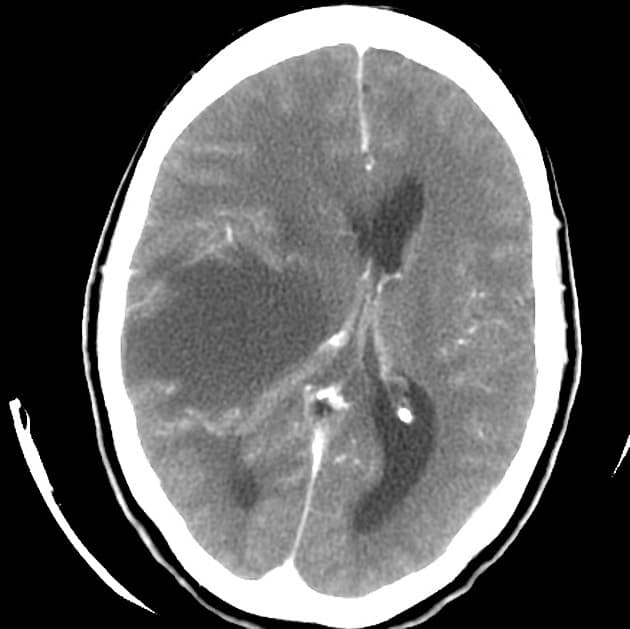

- Hạn chế khuếch tán (restricted diffusion) lan tỏa ở chất trắng vùng trên lều tiểu não, tương ứng với các vùng tăng tín hiệu trên hình ảnh FLAIR.

- Ngoài ra, có các vùng tăng tín hiệu trên FLAIR ở dải vỏ não (cortical ribbon) và các nhân nền (basal ganglia) hai bên, với hạn chế khuếch tán tương ứng nhẹ ở vùng vỏ quanh vận động (peri-rolandic cortex).

Xét theo tiền sử bệnh lý, các phát hiện hình ảnh này phù hợp với bệnh lý thoái hóa trắng sau thiếu oxy chậm (delayed posthypoxic leukoencephalopathy) sau tổn thương não do thiếu oxy-thiếu máu (hypoxic-ischemic encephalopathy).

- "Chụp cộng hưởng từ cho thấy hạn chế khuếch tán lan tỏa ở chất trắng và tăng tín hiệu trên FLAIR, thường kèm theo tổn thương ở vỏ não và nhân nền."